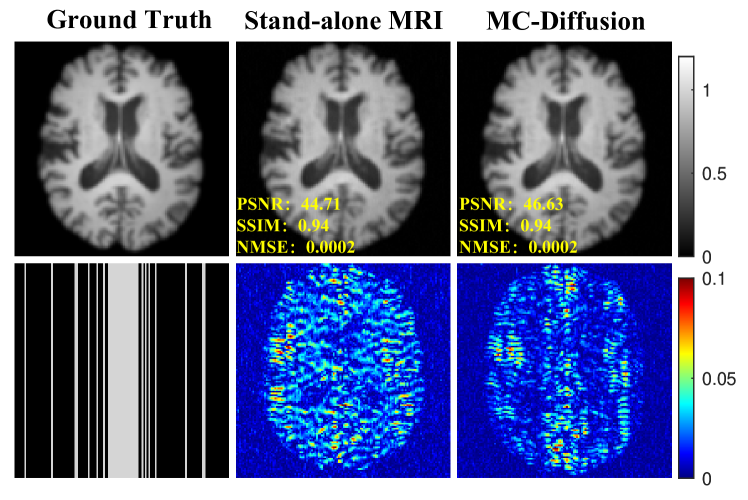

4.2.1 Ablation Study

In this section, we will conduct ablation experiments to affirm the efficacy of this complementary information. In Figure 2, ”Stand-alone” refers to individual reconstruction using the diffusion model with a Cartesian undersampling factor of 4. A comparison of the results from single reconstruction MRI and joint reconstruction MRI reveals that the lack of complementary information significantly compromises the quality of the reconstruction results. Thus, the presence of complementary information intermodal is evident. The quantitative metrics presented in Table 1 correspondingly validate the consistency of the performance with visual perception. Figure 3 illustrates the result of PET reconstruction in an ablation experiment. The results of the PET ablation experiment mirror those of the MRI ablation experiment, indicating that complementary information contributes to PET reconstruction. The quantitative metrics of PET reconstruction are presented in Table 2. This ablation experiment effectively validates the efficacy of the complementary information. It is apparent that the joint reconstruction model consistently outperforms the individual reconstruction model, confirming the existence of a correlation between the two modality images. Exploiting this correlation leads to improved reconstruction results.

Refer to caption

Figure 2: Reconstruction results under cartesian undersampling at 4-fold. The values in the corner are each slice’s PSNR/SSIM/NMSE values. The first row describes the ground truth of MRI and the results of reconstruction by independent model and joint reconstruction model. The second row shows MRI undersampling patterns and error views. The grayscale of the reconstructed images and the error images’ colour bar are on the figure’s right.

Table 1: Quantitative comparison of MRI reconstruction for ablation studies. Highlighting the best results in bold.

Stand-alone MRI MC-Diffusion

PSNR 41.5485±4.5298plus-or-minus41.54854.529841.5485\pm 4.529841.5485 ± 4.5298 42.5714±3.3082plus-or-minus42.57143.3082\textbf{42.5714}\pm\textbf{3.3082}42.5714 ± 3.3082

SSIM 0.9456±0.0359plus-or-minus0.94560.03590.9456\pm 0.03590.9456 ± 0.0359 0.9554±0.0359plus-or-minus0.95540.0359\textbf{0.9554}\pm\textbf{0.0359}0.9554 ± 0.0359

NMSE 0.0004±0.0004plus-or-minus0.00040.00040.0004\pm 0.00040.0004 ± 0.0004 0.0002±0.0003plus-or-minus0.00020.0003\textbf{0.0002}\pm\textbf{0.0003}0.0002 ± 0.0003